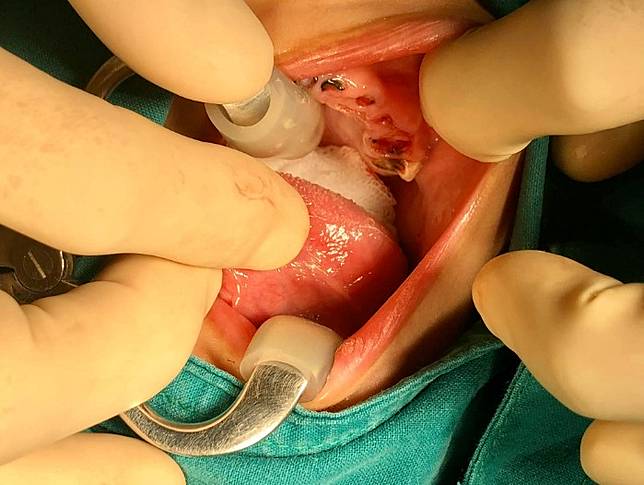

根據《香港經濟日報》引述外電報導,泰國普吉島一名在醫院任職的牙醫日前在臉書上分享案例,一名4歲孩童被父母帶到醫院就醫,張開嘴發現滿口蛀牙,20顆牙齒都被蛀爛,部分乳牙也因不明原因而斷掉,剩下牙床。

(圖/翻攝臉書)

這名牙醫在臉書PO出多張照片,可以看見孩童滿口爛牙,若不拔除可能將往下延伸進牙齦神經,造成下方的恆齒感染,因此只能將20顆牙都拔除。孩童打了14針麻醉針、拔了20顆乳牙及縫上18針縫線,還得吃止痛藥減緩拔牙後的疼痛。